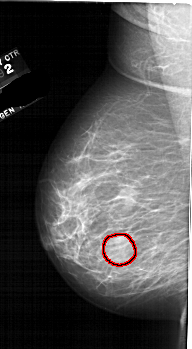

FILE: A_1688_1.LEFT_CC.OVERLAY

TOTAL_ABNORMALITIES 1

ABNORMALITY 1

LESION_TYPE MASS SHAPE ROUND MARGINS ILL_DEFINED

ASSESSMENT 4

SUBTLETY 4

PATHOLOGY BENIGN

TOTAL_OUTLINES 1

BOUNDARY